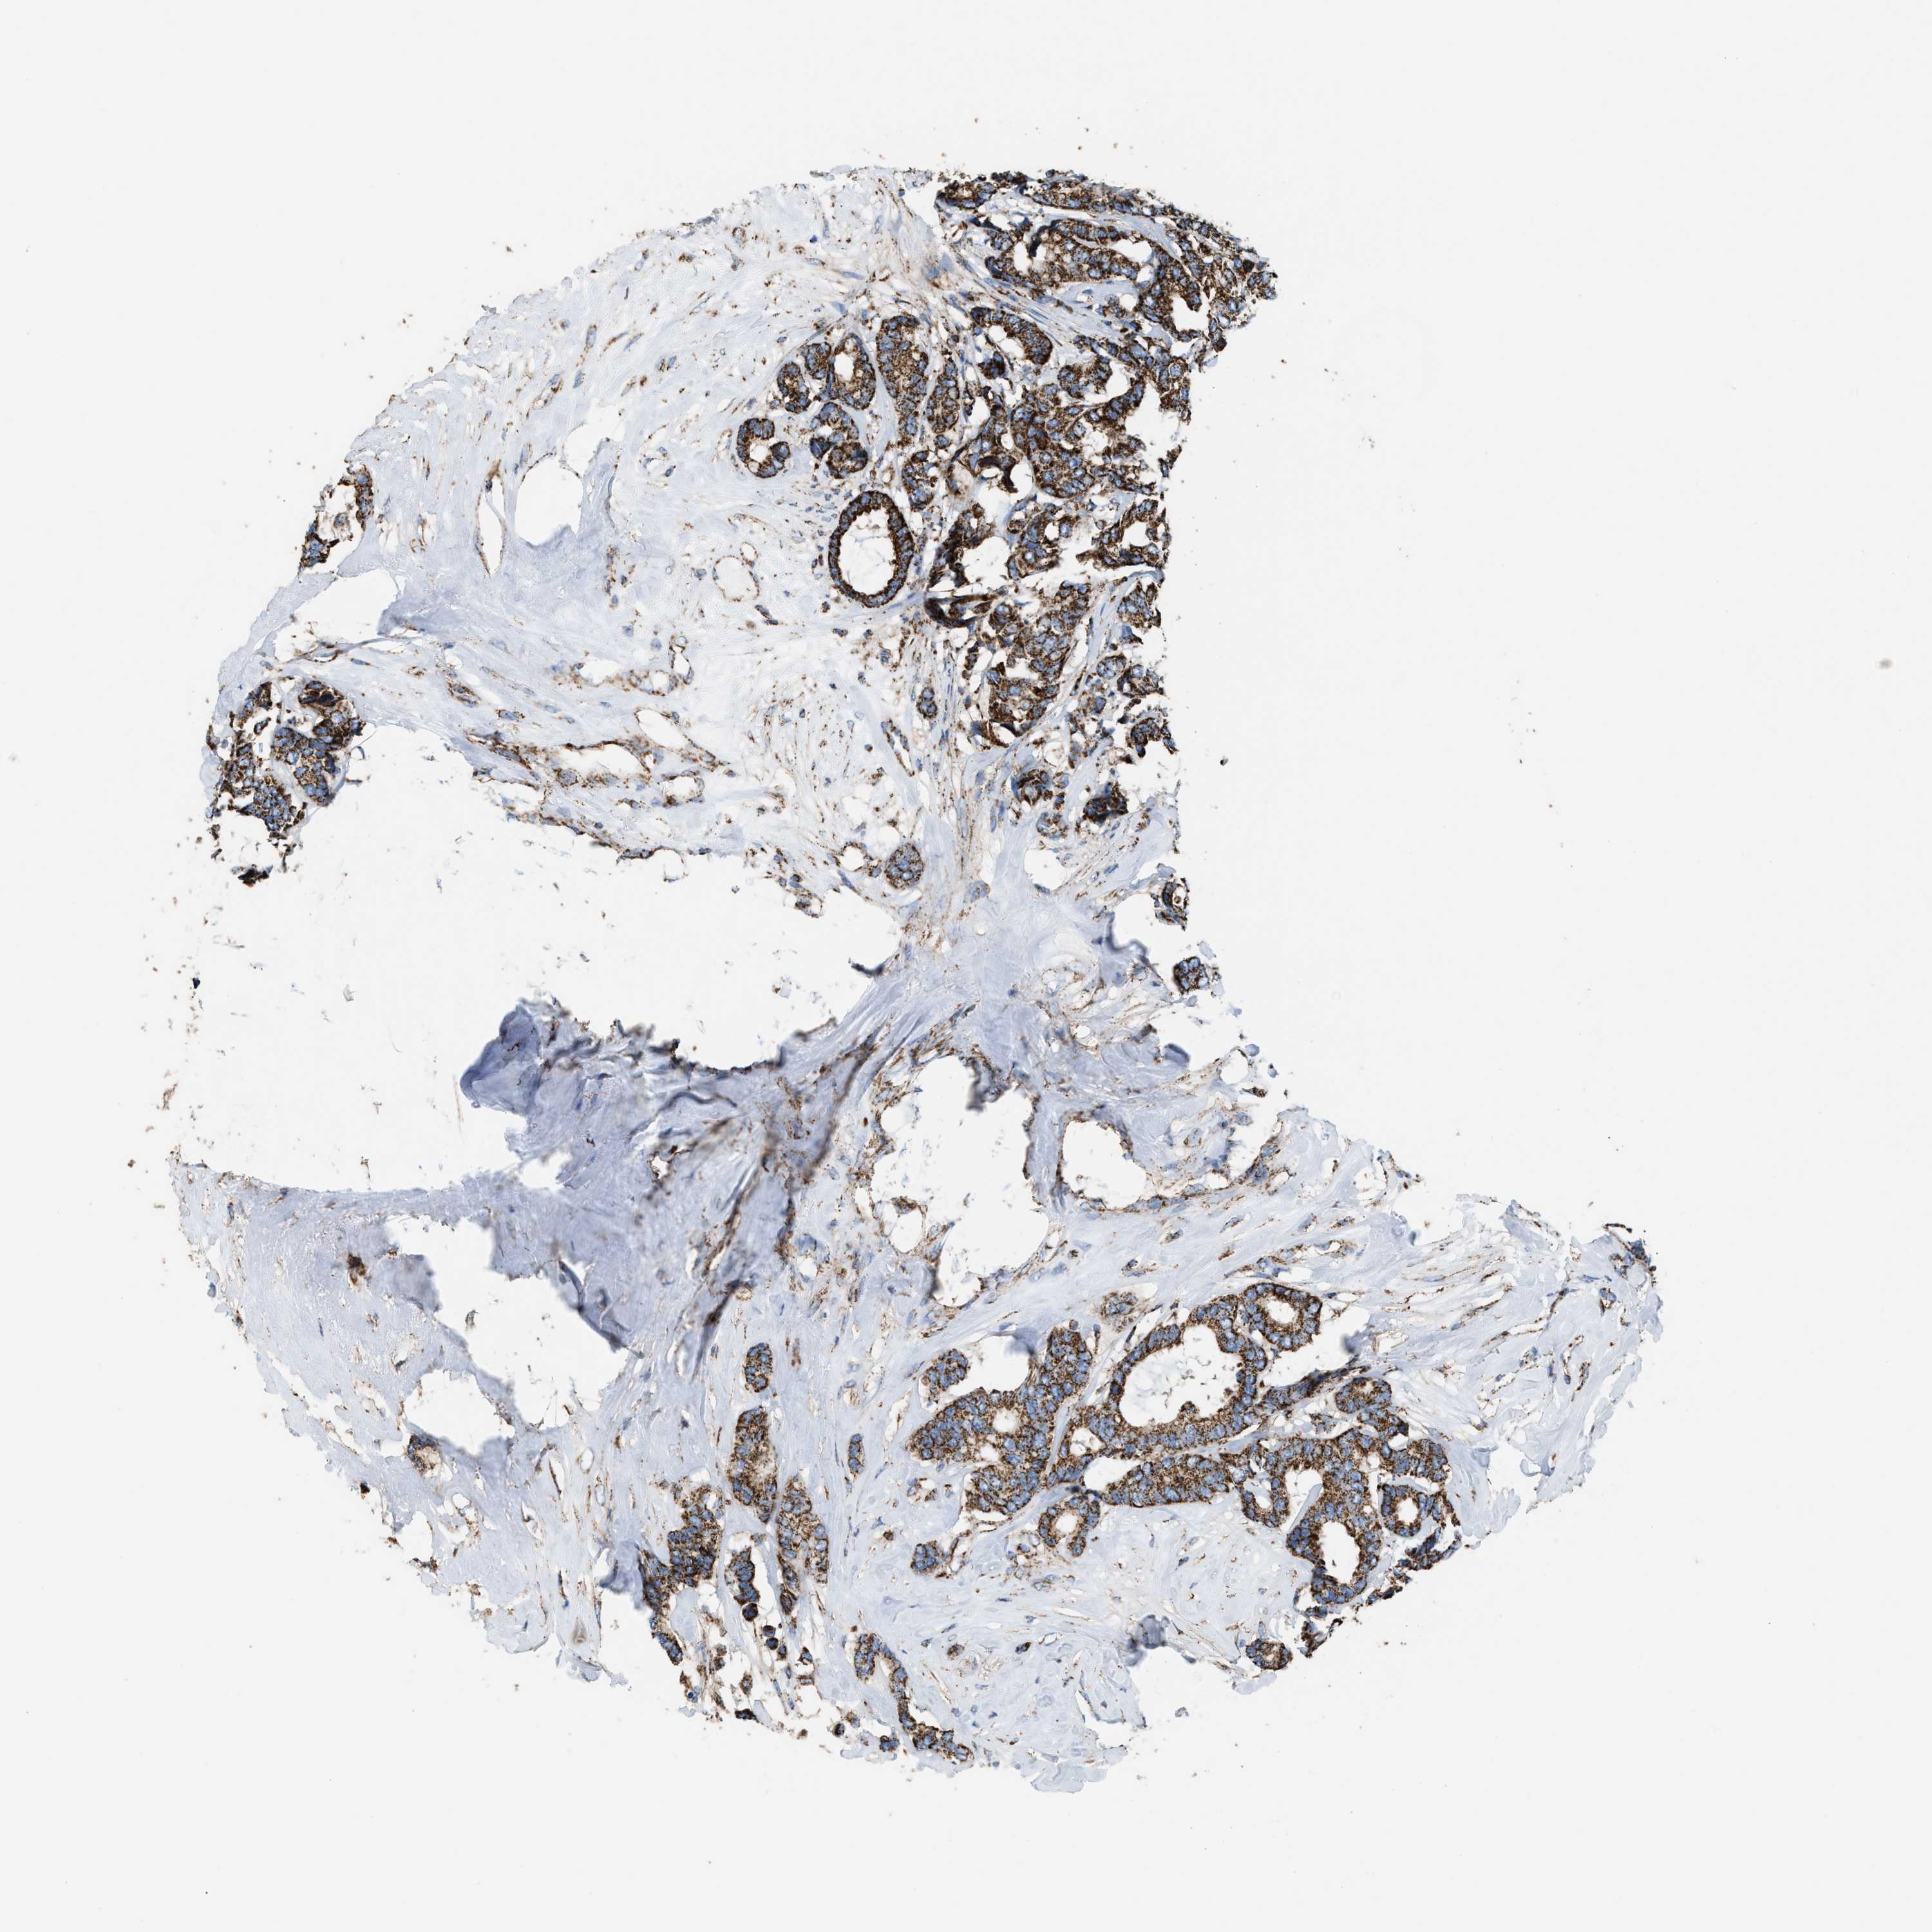

CANCER BREAST CANCER Show tissue menu

BRCA TCGA BRCA VALIDATION PROTEIN EXPRESSION

ANTIBODIES

AND

VALIDATION